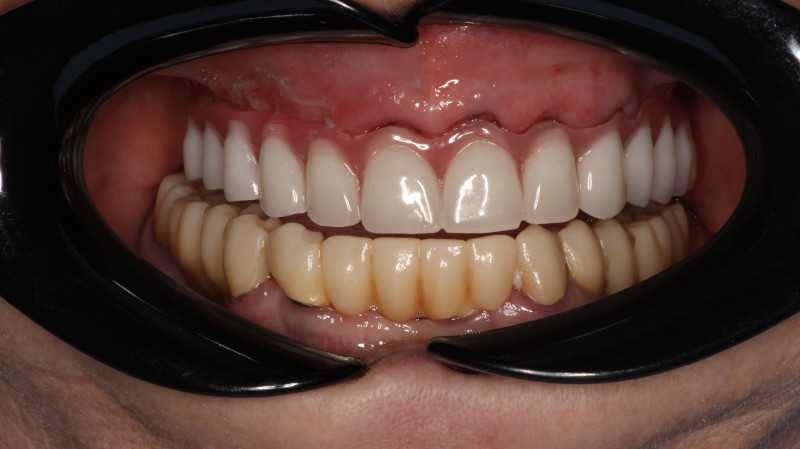

Тотальное протезирование верхней челюсти на 6 имплантатах Astra-Tech (Швеция)